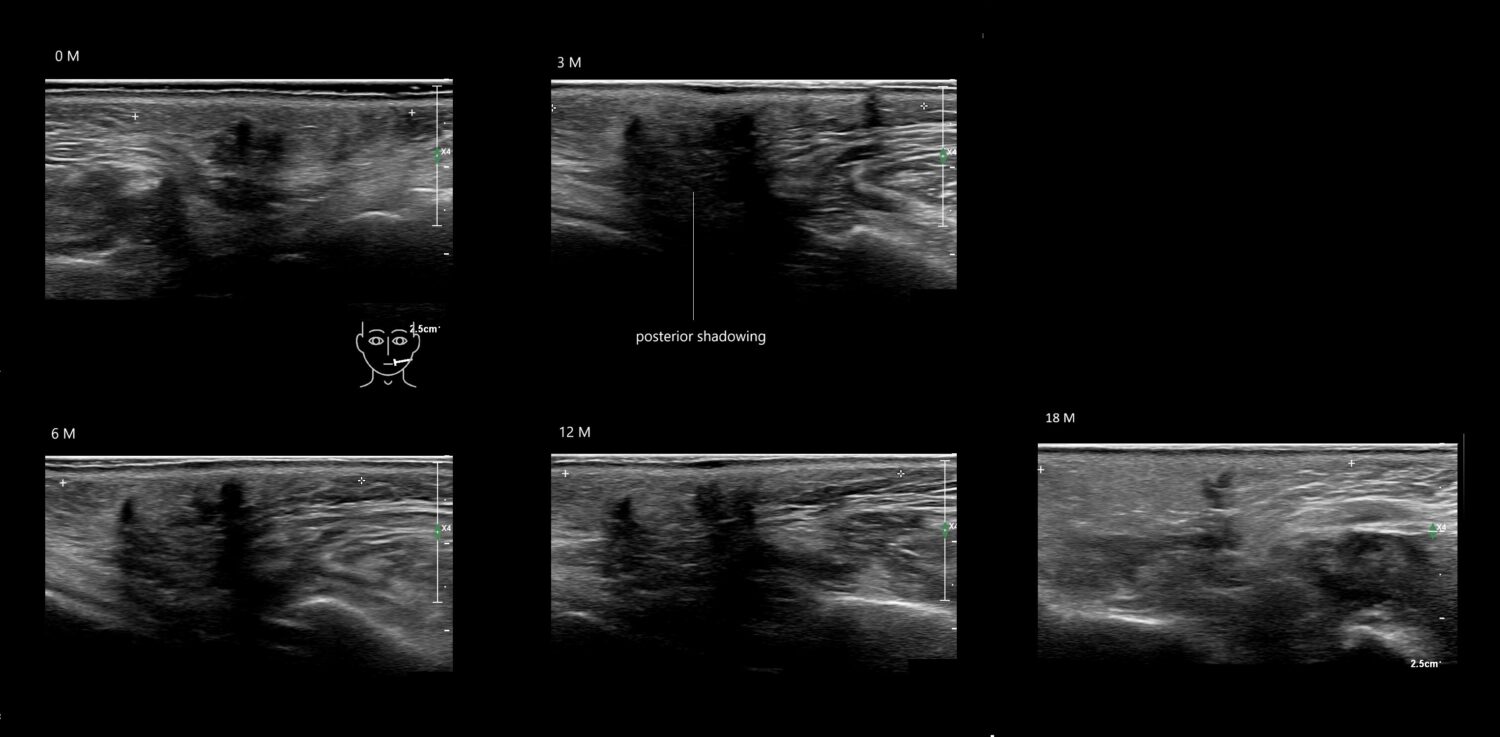

Draw in the image on the right where the fillers are located. To check if your answer is correct, please click on the secondary image.

Draw in the second image below where the fillers are located. To check if your answer is correct, swipe the first image to the right.